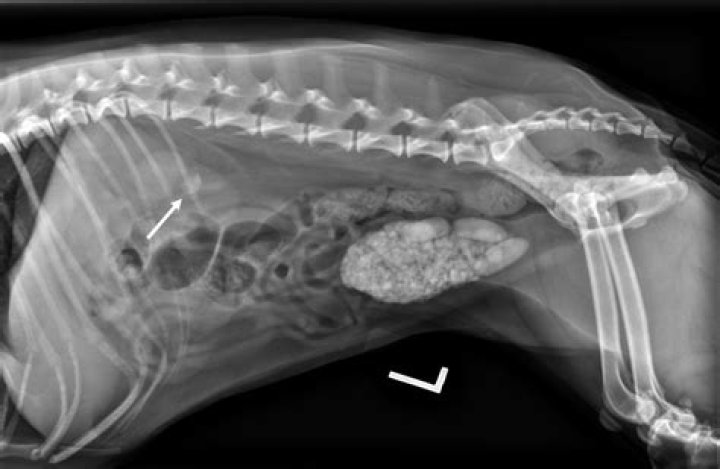

To diagnose a UTI, your veterinarian should collect a sterile urine sample from your pet. The best method to collect urine is by a technique called cystocentesis, during which a needle is inserted through the body wall into the bladder and urine is removed by a syringe.